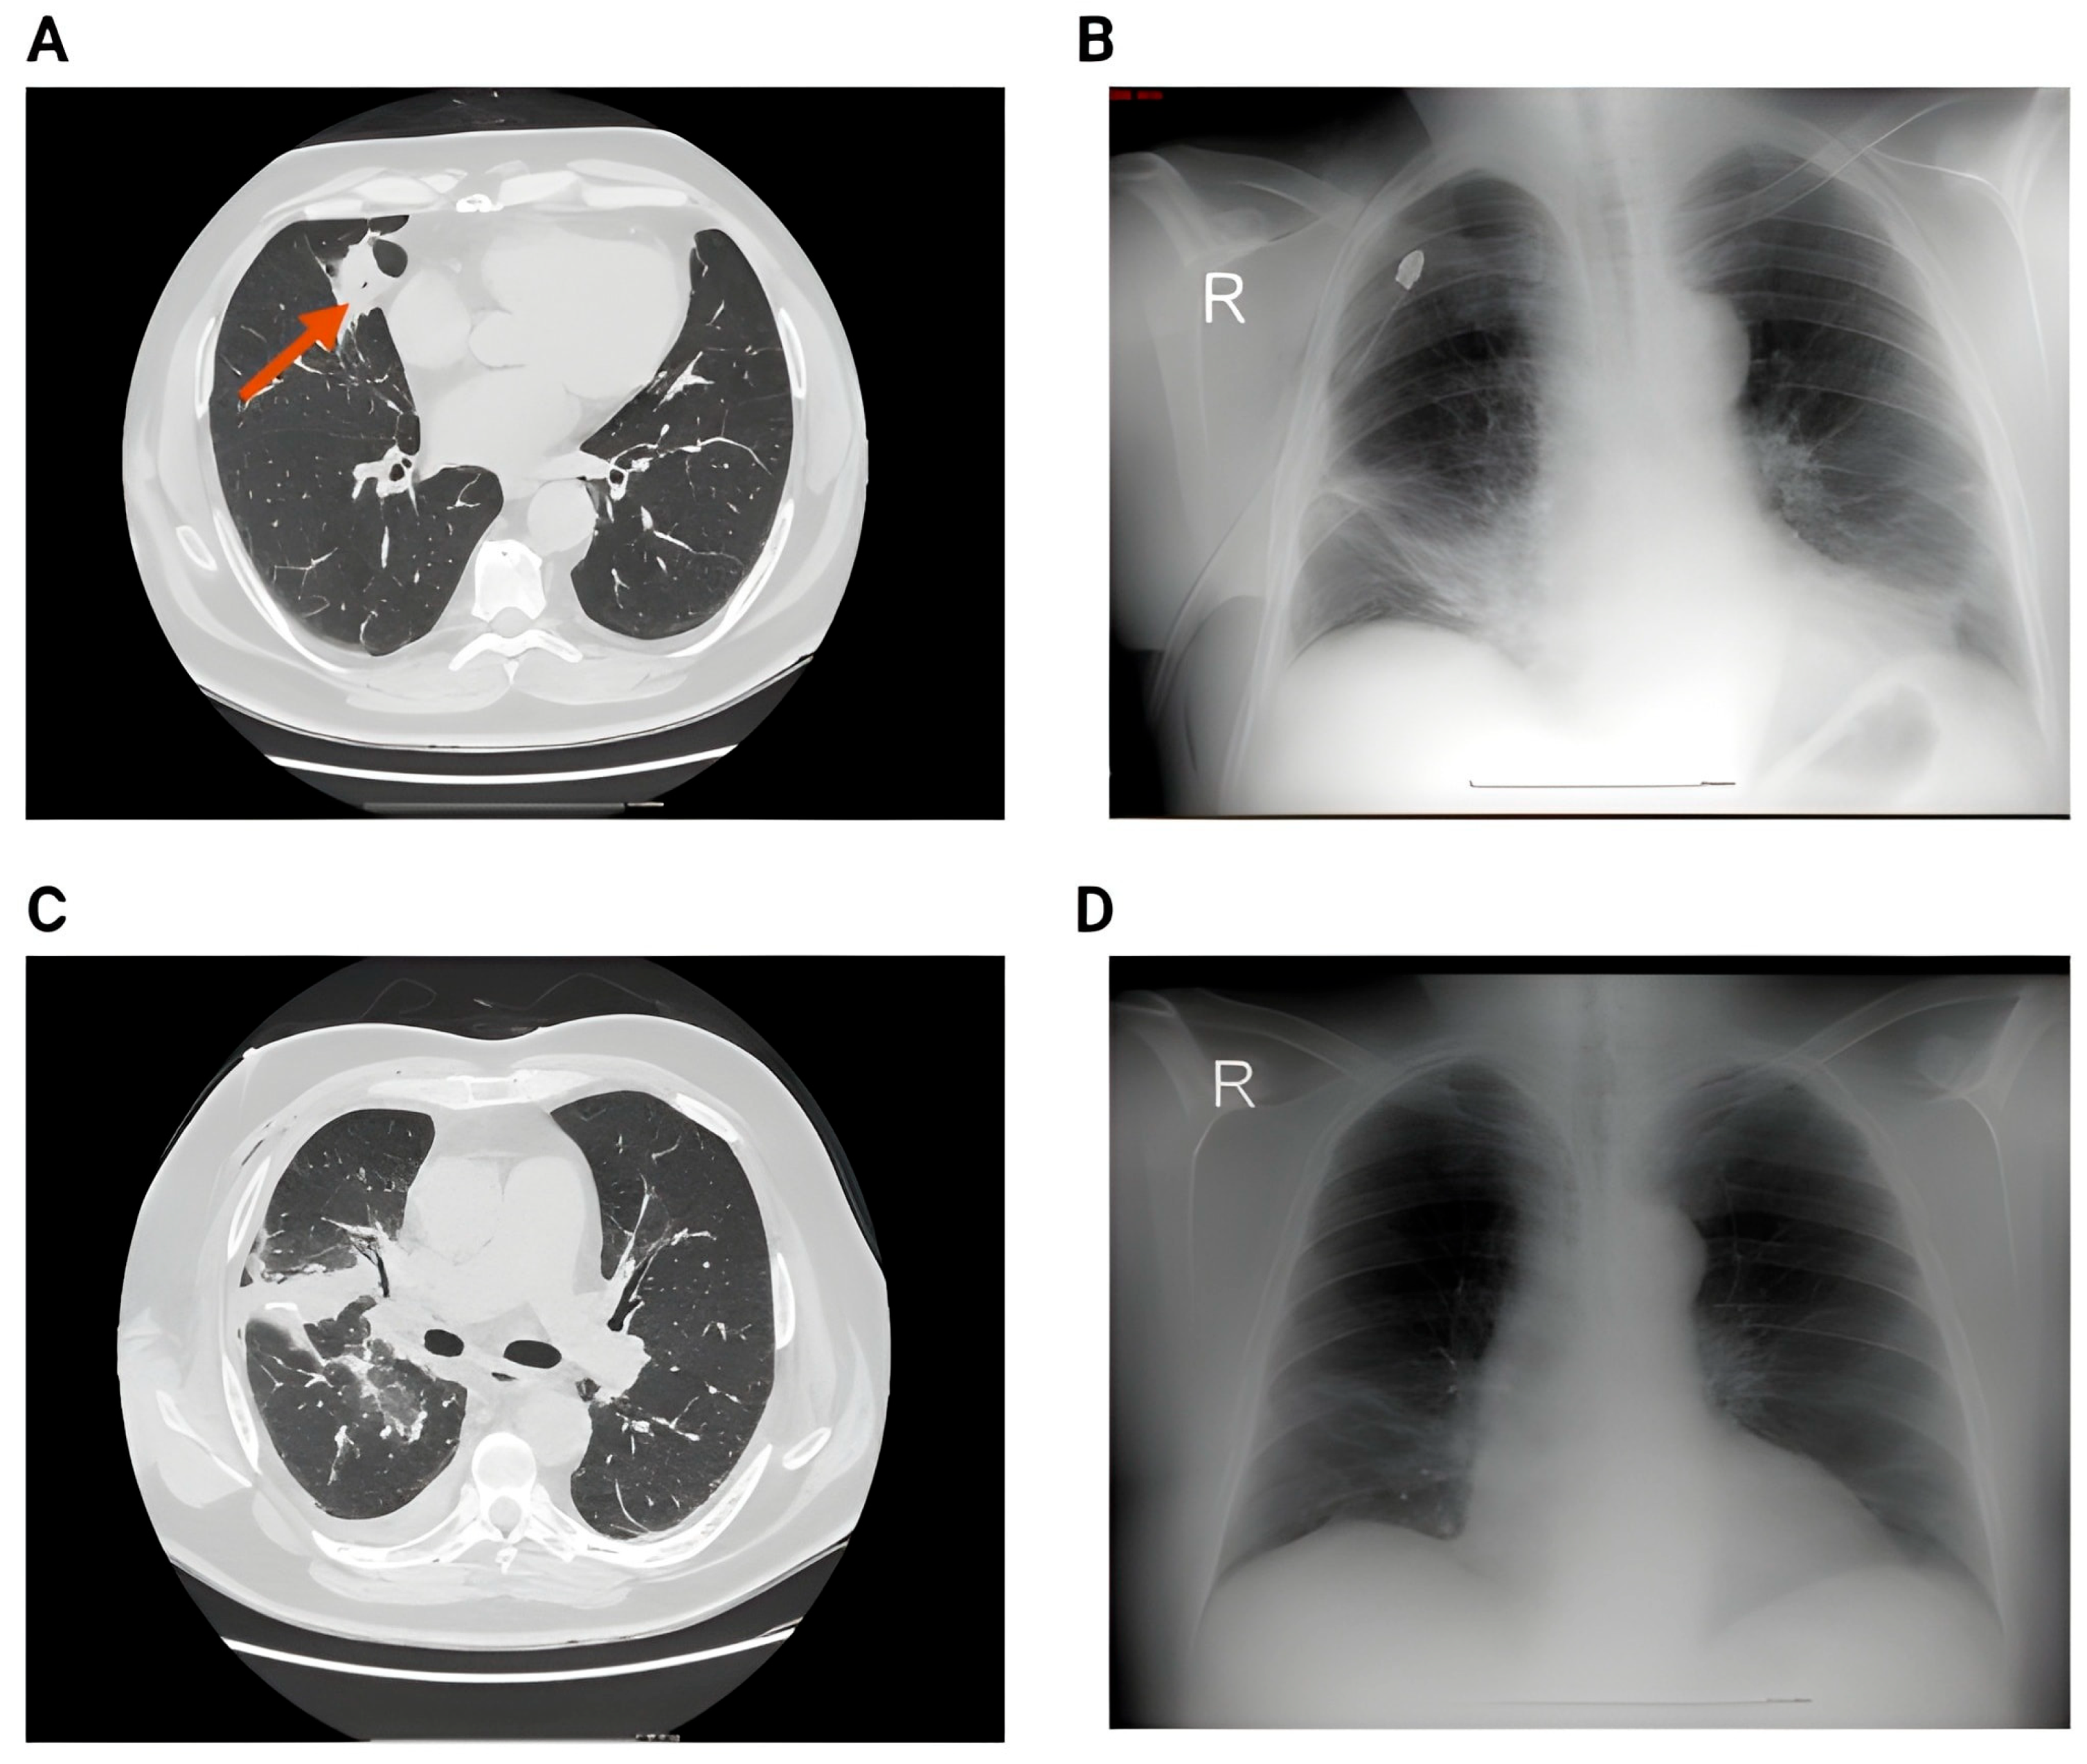

Figure 1 below shows the imagistic changes on x-ray following surgery.

Figure 1. (A) Preoperative chest X-ray showing a pulmonary nodule projected in the middle lobe. No pleural effusion or pulmonary infiltrate. (B) Second postoperative day showing small bilateral pleural effusion, accentuation of the interstitial markings, and a small infiltrate in the right lower lobe; (R = right).